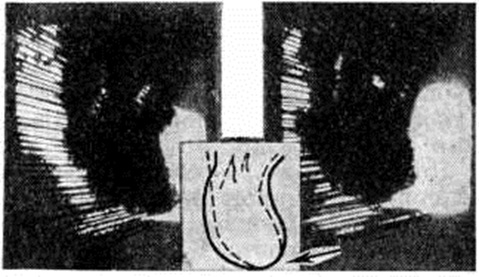

систолический шум (смотри полный свод знаний Сердечные шумы) прослушивается на аорте и может иметь различный тембр, вплоть до очень грубого при склерозе аортального клапана. Систолический шум на верхушке сердца вследствие относительной недостаточности митрального клапана прослушивается довольно часто. При развитии аневризмы в области сердца выявляется парадоксальная пульсация и выслушивается резкий систолический шум. артериальное давление может быть повышено. На рентгенограмме в переднезаднем положении ясно выступает увеличение левого желудочка, верхушка которого закруглена. При рентгенокимографии могут выявляться участки со сниженной амплитудой зубцов — постинфарктные рубцы или аневризма желудочков. Эхокардиография выявляет парадоксальное движение межжелудочковой перегородки в систолу при локализации аневризмы в перегородке в направлении от задней стенки, а не к ней, как в норме. Во время диастолы перегородка остаётся неподвижной. В случаях аневризмы или рубцовых изменений задней стенки левого желудочка иногда удаётся записать парадоксальное движение в систолу или асистолические сегменты, а также гиперкинез перегородки (рисунок 4). Для выявления локализации и объёма поражённых участков миокарда применяют ультразвуковое сканирование. Объем информации значительно возрастает при применении секторального сканирования. Регистрация в режиме реального масштаба времени, двухмерное изображение структур сердца облегчают выявление рубцовых изменений в области верхушки (рисунок 5) и передней стенки, обычно распознаваемых с трудом.